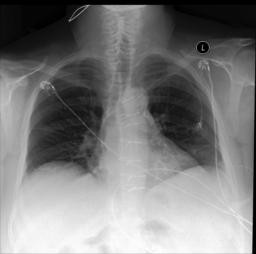

There are low lung volumes. The lungs are clear. There is no pleural effusion or pneumothorax. The cardiomediastinal silhouette is unremarkable. Left central line terminates in the right atrium. Median sternotomy wires and mediastinal clips are noted. A calcified lymph node is noted in the AP window. |

Compared to prior exam from. The lungs are clear. There is no pleural effusion or pneumothorax. The cardiomediastinal silhouette is normal. Median sternotomy wires are intact. |

(a) Input image |

(b) Ground-truth report |

(c) Our report |

Qualitative evaluation. The comparison between our generated report and the ground truth is illustrated in Figure 4. Notably, our generated reports contain similar information to what appears in the ground truth, such as the lung clarity, the appearance of sternotomy wires, and absence of pleural effusion or pneumothorax.